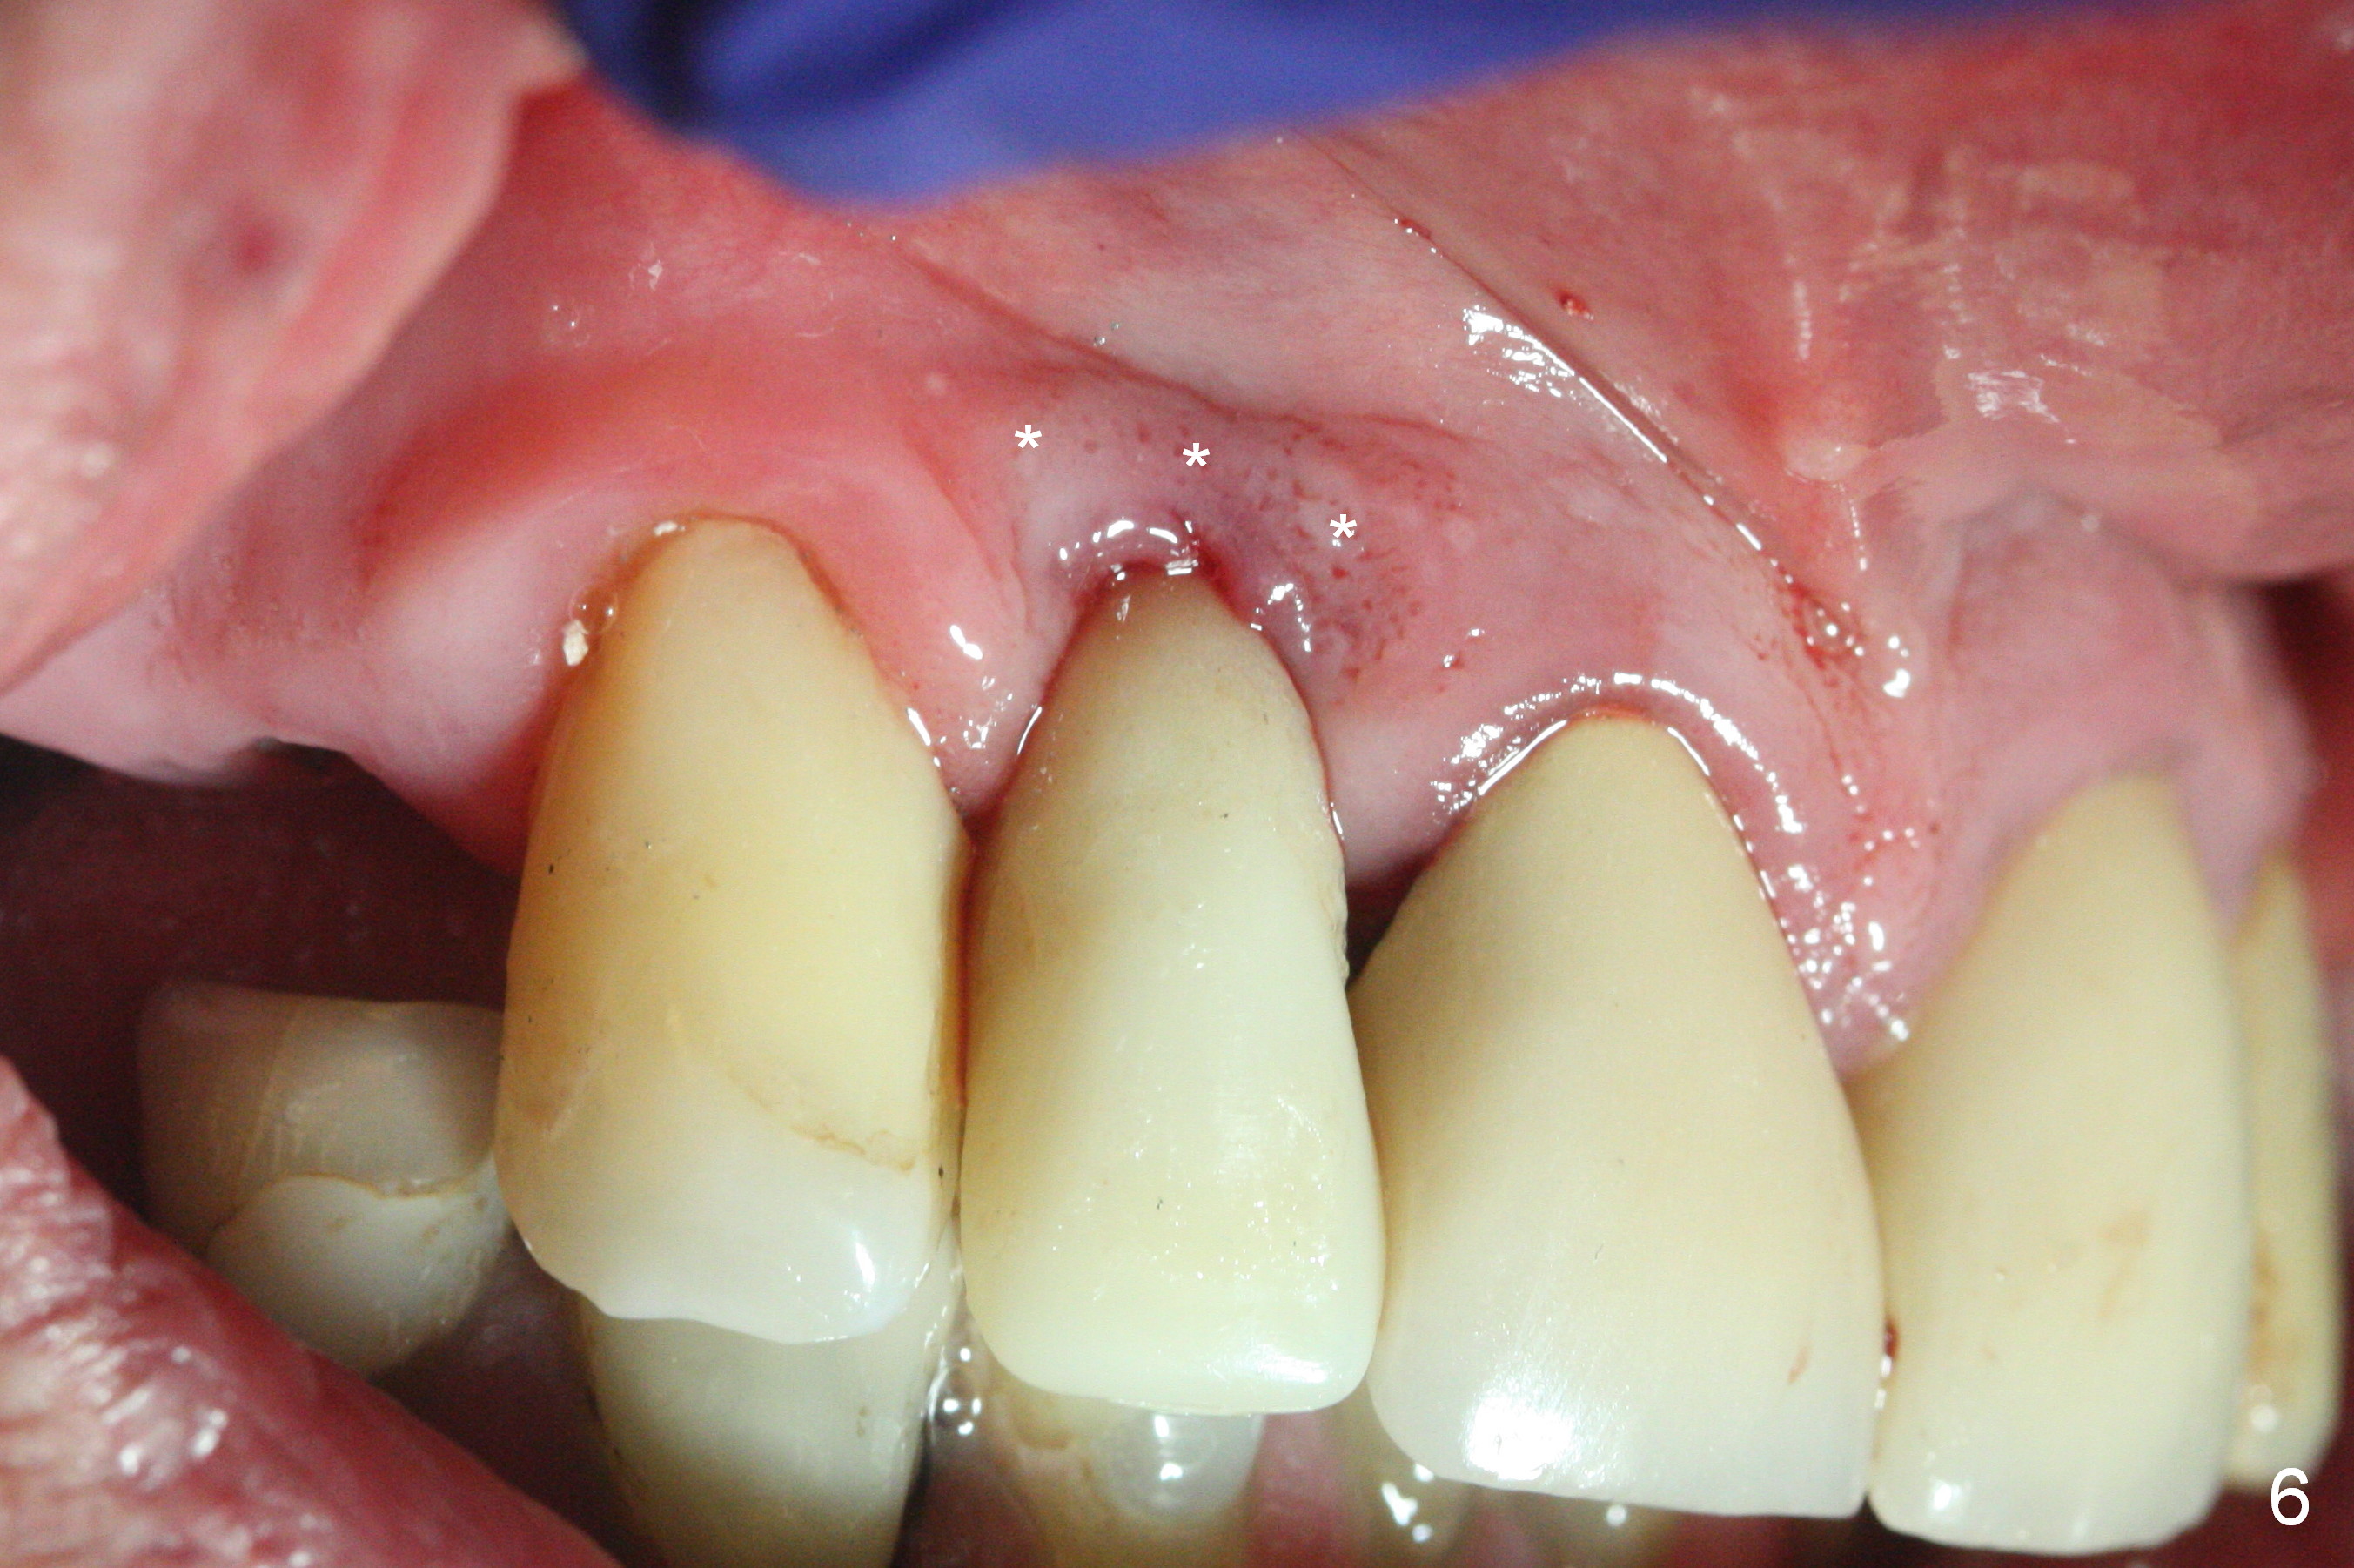

The residual root at #7 is fairly well exposed with buccal gingival recession (Fig.1). The implant placement is flapless (Fig.2-7). What is not shown is that the 3.8x13 mm implant is buccally subcrestally placed (Fig.3). After 1st round of bone graft buccal to the implant, a 4.5x5(5) mm abutment is immediately placed and prepared (Fig.4,5). An immediate provisional is placed after 2nd round of bone graft subgingivally buccally (Fig.6,7). Note the bulging gingiva (*), as compared to that in Fig.4,5. The long implant is chosen because of anterior deep bite (Fig.4) and lack of posterior support (Fig.7).

The gingiva adapts well to the provisional 1 week postop (Fig.8). The buccal gingiva remains recessive and the buccal plate is concave 5.5 months postop (Fig.9-11). It appears that the coronal portion of the buccal plate is resorbed 12 months postop (6 months post cementation, Fig.12 >). Socket shield or smaller diameter implant should have been done to avoid bone loss. Reanalysis of CBCT reveals that implantation apparently increases the bone width and that the buccal plate resorption is not so severe (Fig.13,14 (>: coronal end of the buccal plate)). Panoramic X-ray is taken 2 year 5 month post cementation.